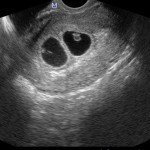

Si tratta di un test composto da 2 metodiche: un esame di laboratorio (Bi-test) ed una Ecografia mirata per lo studio di dettagli fetali, in particolare la translucenza nucale, la cui anormalità è correlata alla possibilità di anomalie fetali. Tale esame ha lo scopo di identificare le gravidanza a maggior rischio di patologie cromosomiche fetali: trisomia 13, trisomia 18 e trisomia 21 (conosciuta anche come Sindrome di Down).

E’ un esame ecografico che consiste nella misurazione, tra la 11esima e la 13esima settimana, di uno spazio situato nella regione posteriore del collo fetale. In tale sede è presente una sottile falda di liquido che è presente nella regione nucale di tutti i feti e che appare all’esame ecografico come una sottile zona liquida detta translucenza. Quando tale falda fluida è aumentata (aumento di spessore della translucenza nucale) può esservi un maggior rischio di patologie cromosomiche fetali o altre patologie, ad esempio cardiopatie malformative. Oltre alla translucenza nucale, si esegua ovviamente una accurata valutazione della morfologia fetale, per quanto possibile in relazione all’epoca di gravidanza.

L’associazione del Bi-Test con la misurazione ecografica della Translucenza nucale ha una sensibilità per la Sindrome di Down del 90% (è cioè in grado di individuare 90 feti su 100 affetti da sindrome di Down).